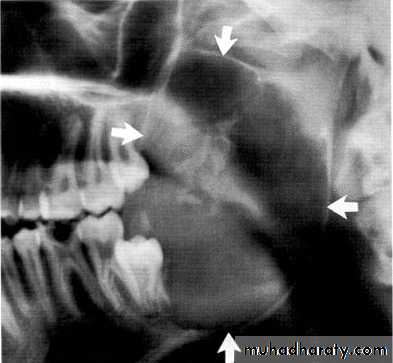

Large multilocular aneurysmal bone cyst

in the ramus with marked expansion andthe displacement of/8.

It is non-neoplastic ,exaggerated , localized, proliferative lesion of vascular tissue, containing giant cells.

It’s a variation of the central giant cell granuloma , can be diagnosed only by histological examination